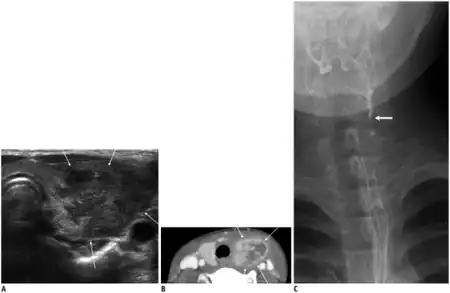

Patients who are suspected of having AIT often undergo tests to detect for elevated levels of white blood cells as well as an ultrasound to reveal unilobular swelling.[1][4] Depending on the age and immune status of the patient more invasive procedures may be performed such as fine needle aspiration of the neck mass to facilitate a diagnosis.[4] In cases where the infection is thought to be associated with a sinus fistula it is often necessary to confirm the presence of the fistula through surgery or laryngoscopic examination.[6] While invasive procedures can often tell definitively whether or not a fistula is present, new studies are working on the use of computed tomography as a useful method to visualize and detect the presence of a sinus fistula.[6]

- Ultrasonographic examination often shows the abscess or swelling in thyroid

- Barium swallow will show fistula connection to the piriform sinus and left lobe